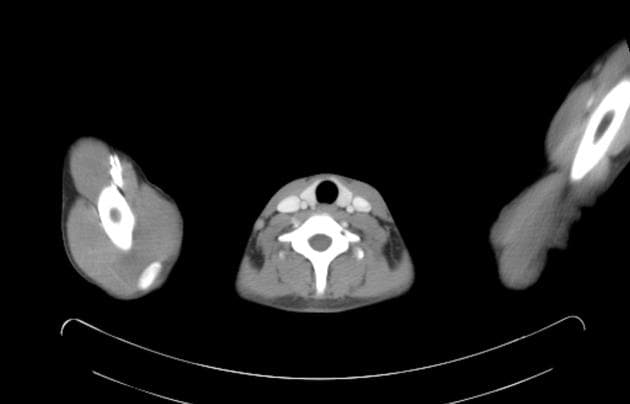

Coronal C+ arterial phase

- Tấm lợp nội trung mạc tách rời kéo dài từ rốn động mạch chủ đến cung động mạch chủ với hình ảnh hai lòng mạch điển hình

- Lòng giả lớn bên phải chèn ép lòng thật nhỏ hơn ở bên trái

- Khối máu tụ thành mạch (intramural hematoma) dọc theo thành sau của động mạch chủ lên

- Dịch tăng tỷ trọng (hyperdense fluid) dọc theo và xung quanh thân động mạch phổi và cả hai động mạch phổi, kèm lòng mạch động mạch phổi phải tương đối hẹp

- Phình tách động mạch chủ từ rốn động mạch chủ đến cung động mạch chủ, Stanford type A

- Vết rách vào ở rốn động mạch chủ sau, hai vết rách thoát ra ở cung động mạch chủ

- Khối máu tụ thành động mạch chủ (aortic intramural hematoma) ở thành sau bên

- Khối máu tụ thành động mạch phổi (pulmonary artery intramural hematoma) phối hợp

- Lòng giả lớn (vùng phủ màu vàng) nằm bên trái tấm lợp nội trung mạc tách rời

- Vết rách vào ở rốn động mạch chủ sau (mũi tên đỏ) và các vết rách thoát ra ở cung động mạch chủ (mũi tên xanh)

- Khối máu tụ thành động mạch chủ thấy rõ ở bờ sau của động mạch chủ lên (vùng phủ màu đỏ)

- Khối máu tụ thành động mạch phổi chủ yếu quanh thân động mạch phổi và động mạch phổi phải (vùng phủ màu xanh)